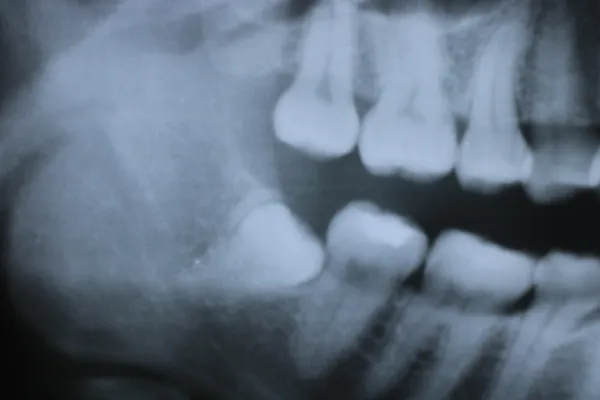

7親知らず

Case7